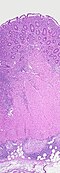

U svrhu potvrđivanja dijagnoze se, tijekom kolonoskopije često uzimaju biopsije debelog crijeva . Neke karakteristične patološke promjene koje se pronalaze mikroskopskom pretragom ukazuju na Crohnovu bolest. Jedna od njih je transmuralna upala, što znači da se upalne promjene protežu kroz cijelu debljinu stijenke crijeva.[1] U aktivnom stadiju bolesti nalaze se i ulceracije. Između dijelova crijeva zahvaćenih bolešću i susjednih dijelova crijeva granica je jasna – što je karakteristični znak i naziva se preskačućim lezijama. Mikroskopskom pretragom se u tkivu crijeva uzetog biopsijom nalaze upalne promjene u sluznici, obilježene žarišnim nakupljanjem neutrofila (vrste upalnih stanica) unutar epitela. Do ovog nakupljanja tipično dolazi u područjima kojima podleže nakupine limfatičnog tkiva. Neutrofili, zajedno s limfocitima, mogu infiltrirati Lieberkuhnove kripte, što se naziva kriptapscesima. Nakupine promijenjenih makrofaga, zbog svoje sličnosti s epitelnim stanicama zvanih epiteloidne stanice koje se nalaze u oko 50% slučajeva Crohnove bolesti nazivaju se granulomi. Epiteloidne se stanice mogu međusobno stapati, tvoreći divovske stanice s više jezgara. Granulomi su najkarakterističniji nalaz u Crohnovoj bolesti. U ovoj bolesti oni ne sadrže središnju “kazeoznu” nekrozu (koja je tako nazvana zbog svog makroskopskog izgleda sličnog svježem, kravljem siru), a koja se ponajprije nalazi kod upala obilježenih stvaranjem granuloma, kao što je tuberkuloza. U biopsijama se mogu naći znakovi kroničnog oštećenja sluznice, poput sniženja i zaravnjenja crijevnih resica u tankome crijevu i nepravilnog grananja kripta.[85][86]

Endoskopski učinjena biopsija pokazuje granulomatoznu upalu debelog crijeva u bolesnika od Crohnove bolesti.